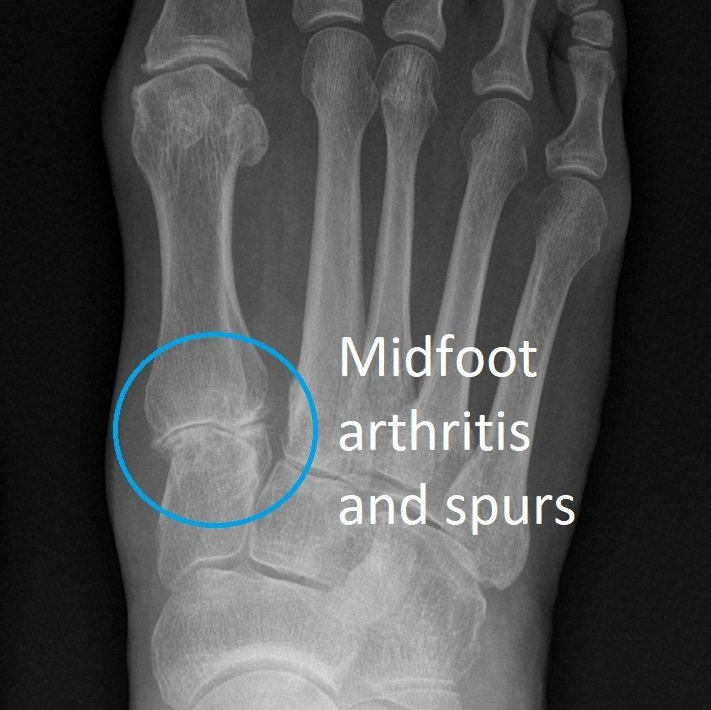

It is more common in women, people aged over 60, those with midfoot arthritis, and who are over-weight.

- weight-bearing X-rays of the foot looking for midfoot arthritis.

Other possible procedures include:

- removal of bone spurs